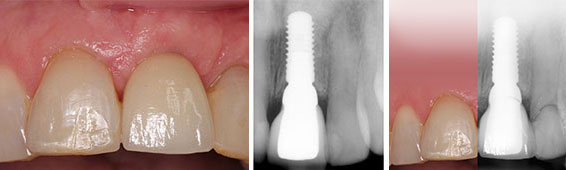

Dental implants are the most successful way of replacing the missing teeth. They are titanium-modified screws that replace the root of the tooth without disturbing the integrity of neighbouring teeth. Once the titanium screw heals, it is fused to the existing alveolar bone and becomes the root of the tooth, and then a prosthetic crown is connected to complete the procedure. Careful risk assessment and regular maintenance is key for long term success of dental implants, as well as a close collaboration with your referring dentist or our in-house prosthodontist to ensure seamless transition to the restorative phase of dental implants.